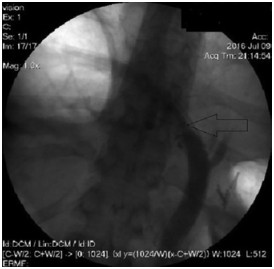

Abstract: Hilar cholangiocellular carcinoma (CCC) is a malignant neoplasm of epithelial origin occurring at the confluence of the right and left hepatic bile ducts. Typically, these tumors are small, poorly differentiated, exhibit aggressive biologic behavior with non-specific symptoms and tend to obstruct the intrahepatic bile ducts. Surgery is the only available curative option. Unfortunately, in less than half of the patients a complete resection is possible with poor survival rate in unresectable cases. In this report, we present the case of a 58-year-old woman with a history of unresectable hilar cholangiocarcinoma. Initially she was treated with intraductal dilatation of malignancy and placement of a plastic stent and chemotherapy (Gemcitabin® and Platinol®). Two years later she underwent a second-line chemotherapy with Gemcitabin® and Oxyplatin® because of tumor progression. Despite a second line chemotherapy and placement of an uncovered self-expandible metal stent (ucSEMS) that was extended later on by stent-in stent technique, there was tumor progression which led to a complex course with relapsing obstructive cholangiosepsis and cholestasis. Because of tumor ingrowth, endobiliary radiofrequency ablation of the malignant stenosis was performed in repeated sessions. This case illustrates that radiofrequency ablation of solitary malignant biliary obstruction is feasible, safe and allows an improvement of quality of life in non-operable patients.